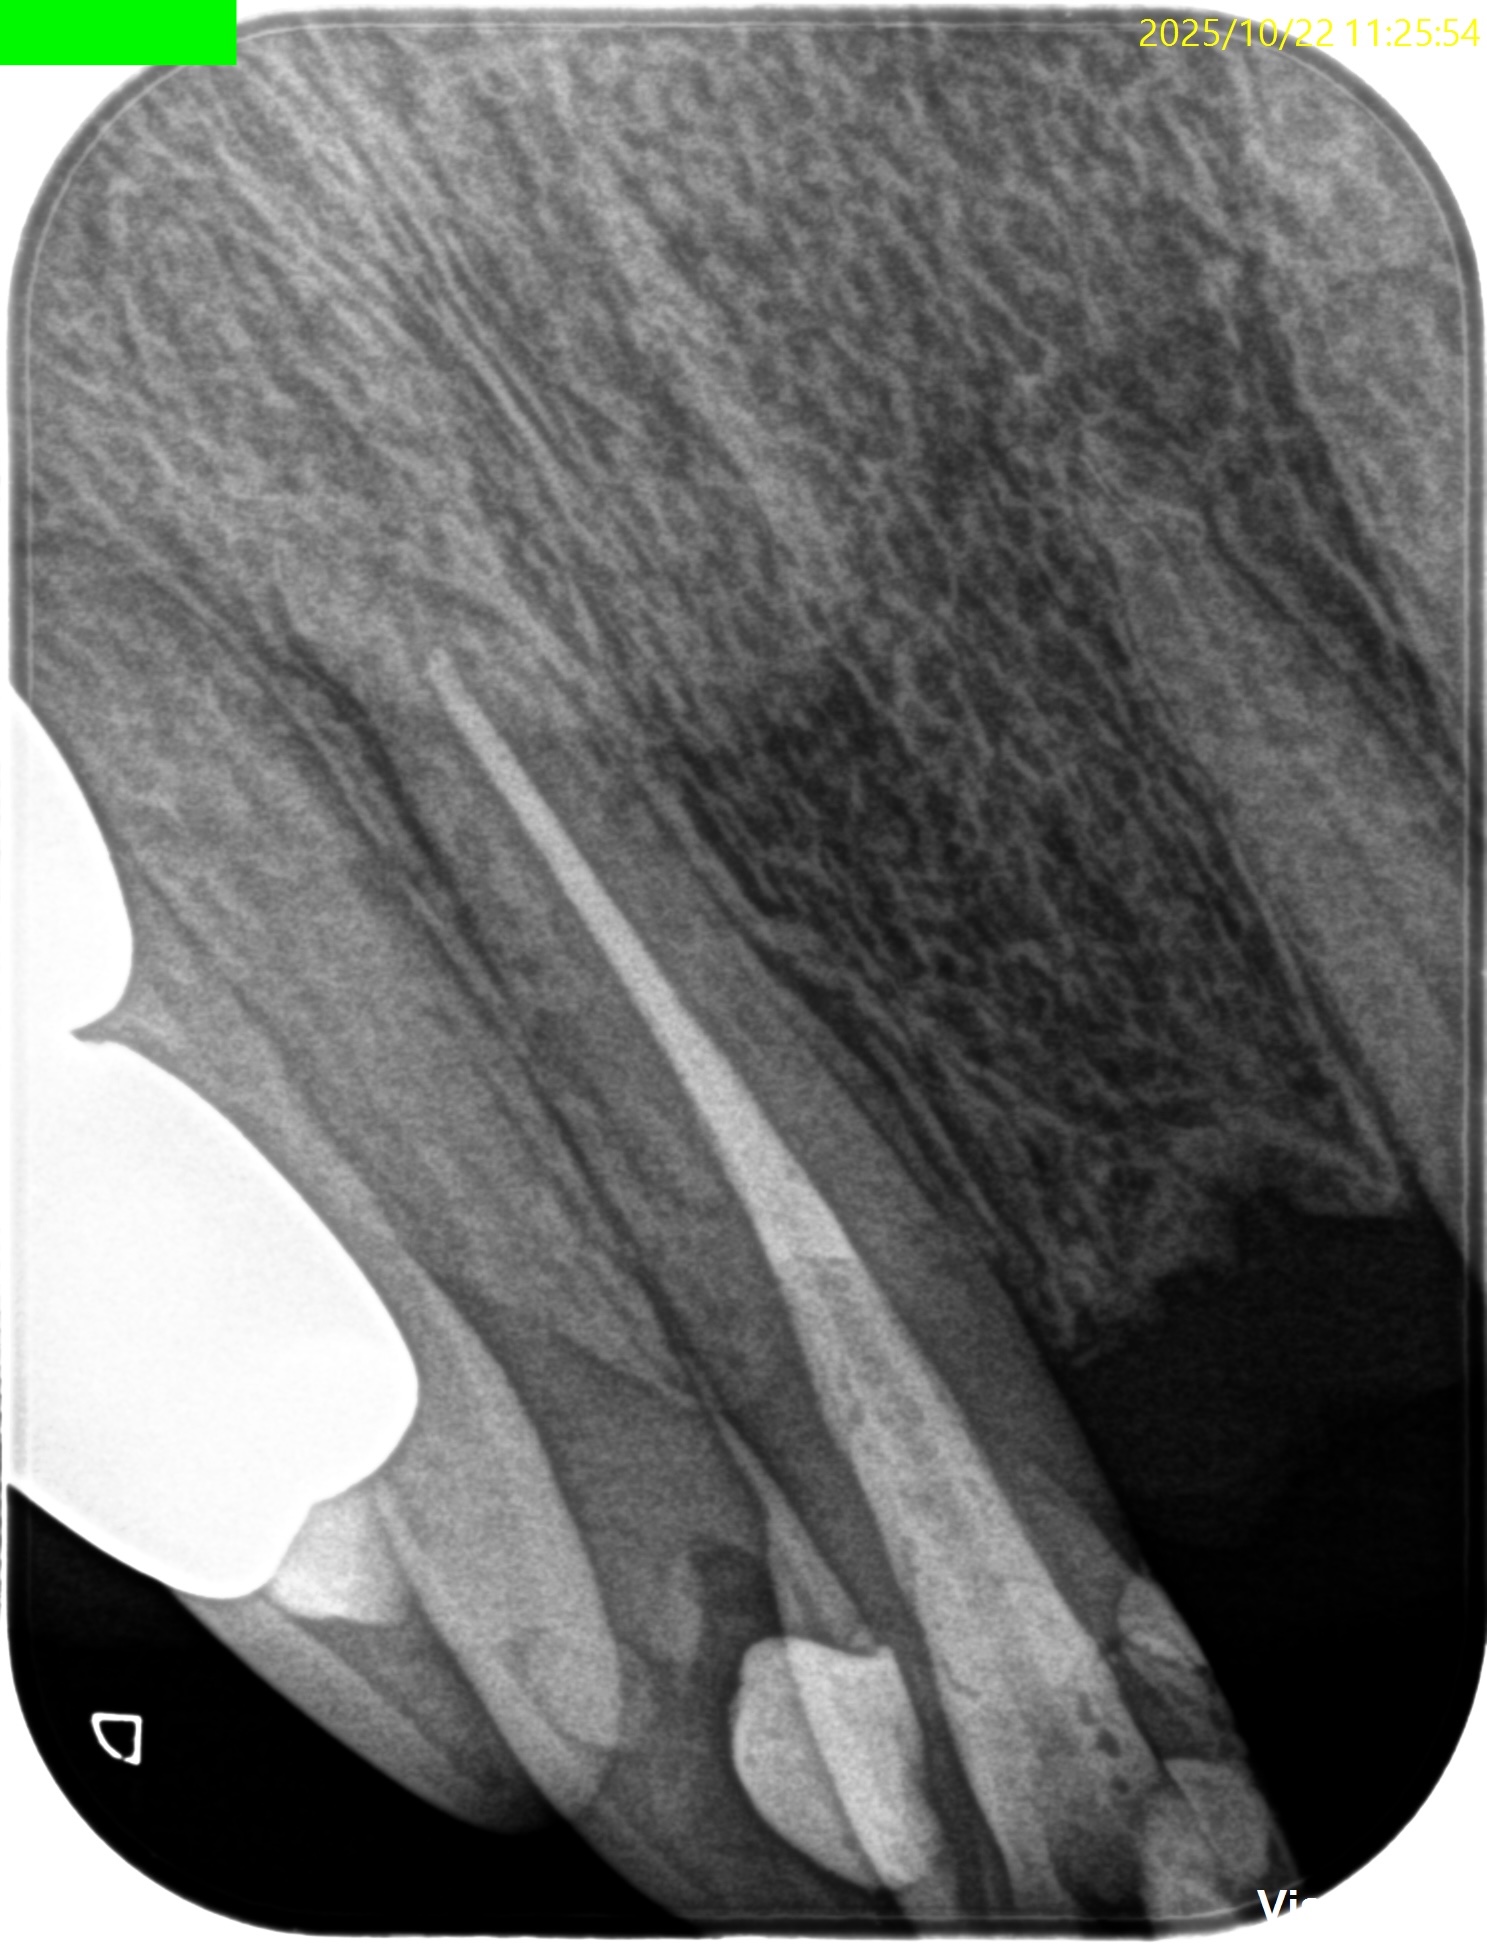

PA(2025.10.22)

この部分を攻略できれば勝機がある可能性が90%あるだろう。

攻略できなければ60%だ。

どっちか?は治療しなければわからない。

それが根管治療の奥深い?ところなのかもしれない。